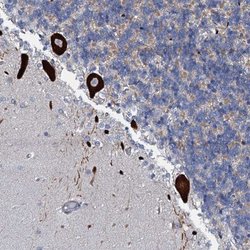

Immunohistochemistry

ABIN4341391 IHC

Other validation